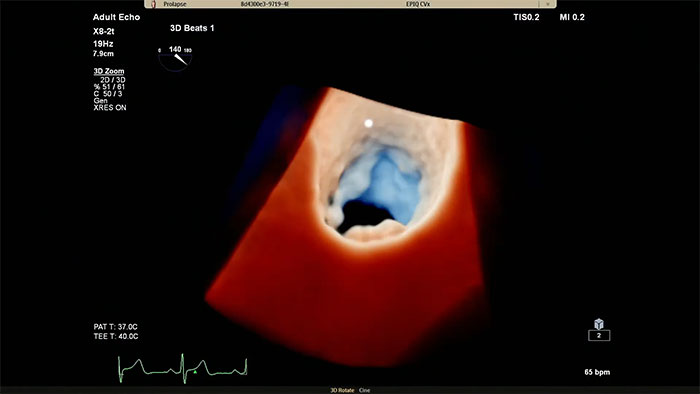

EPIQ CVx - TrueVue Color

View enhanced visualizations of structures and flow with TrueVue Color

EPIQ CVx - TrueVue Glass

Visualize cardiac morphology using ultrasound with TrueVue Glass